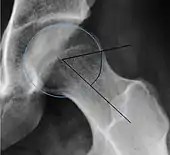

Alpha angle

Measured in 45° Dunn view.

Degree of bulging of the femoral head-neck junction: In normal conditions there is a symmetric concave contour at the junction of the femoral head and neck. Loss of this concavity or bone bulging may lead to cam type impingement. The degree of this deformity can be measured by the alpha angle. Although it can be measured in the cross-lateral view, the 45° Dunn view is considered more sensitive and the frog leg view more specific in determining pathologic values.

• Normal: ≤68° in men, ≤50° in women

• Borderline: 69° to 82° in men, 51° to 56° in women

• Pathological: ≥83° in men and ≥57° in women